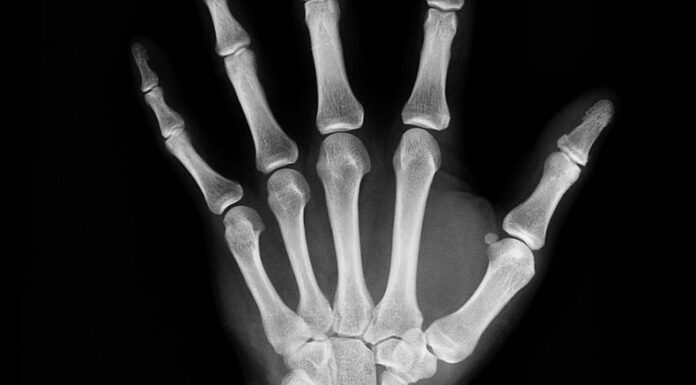

La artritis idiopática juvenil puede afectar cualquier articulación del cuerpo, pero con frecuencia perjudican en las rodillas, manos y pies de los niños.

Los especialistas acotaron que se diagnostica mediante un examen físico y una revisión de los síntomas, las radiografías y los análisis de laboratorio.